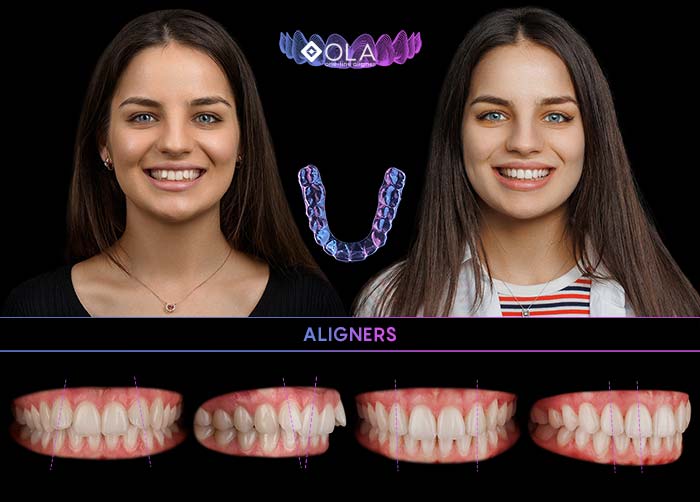

Alignerele OLA

Metoda inovativă și invizibilă de îndreptare a dinților:

Sistemul de alignere OLA, creat de Dr. Sachin Sachdev

5000+

pacienți au obținut o dantură frumos aliniată cu alignerele OLA

- 100% personalizate (se realizează în laboratorul dentar)

- Transparente, estetice și practic invizibile

- Eficiente la orice vârstă

- Detașabile (se îndepărtează ușor)

- Confortabile (material moale și neted)